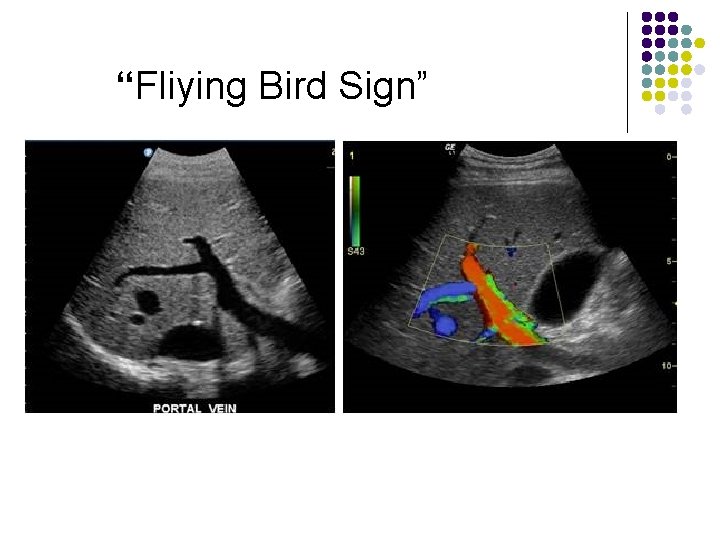

“Fliying Bird Sign”